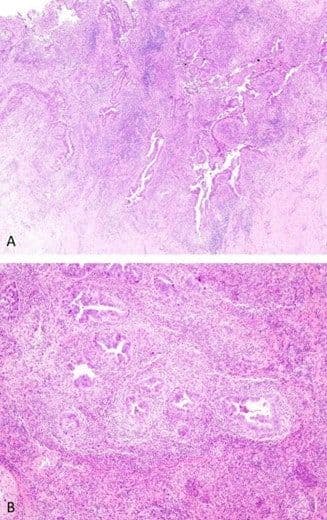

High-risk squamous intraepithelial lesion (HSIL) is associated with infection by high-risk HPV serotypes. HSIL typically presents as a flat lesion (Figure 6), but may also be exophytic, where the colposcopic and microscopic distinction from papillary squamous cell carcinoma (see below) may be challenging.

Histologically, HSIL is characterized by significant architectural disorder, cell crowding, and cytologic atypia in the basal layer. There is generally impaired (CIN 2) or no (CIN 3) maturation toward the epithelial surface, and mitoses are frequently conspicuous in the superficial epithelial layers. Microscopic involvement of endocervical crypts is common (Figure 7) and should be noted in the pathology report.

Figure 7

A Ki67 immunostain is typically briskly positive throughout the epithelial thickness. Strong diffuse p16 positivity (particularly in the lower epithelial layers, but often throughout the full epithelial thickness) is characteristic of HSIL and has a high negative predictive value in distinction of HSIL from reactive epithelial atypia or LSIL.